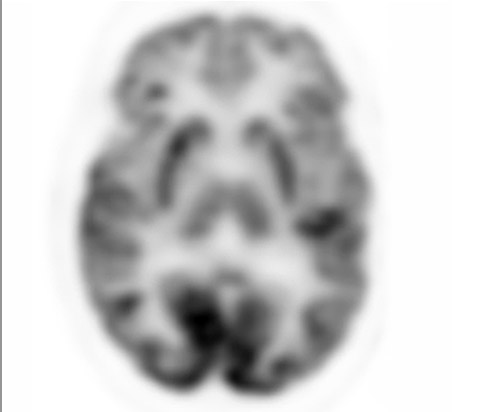

Mit der etwa zweimal höheren volumetrischen Auflösung gegenüber dem analogen System* zeigt der Vereos PET/CT-Scanner außergewöhnliche Details und hervorragende anatomische Bilder, wie die hier abgebildeten tiefen Strukturen des Gehirns. *GEMINI TF 16

Analoger PET-Scan*